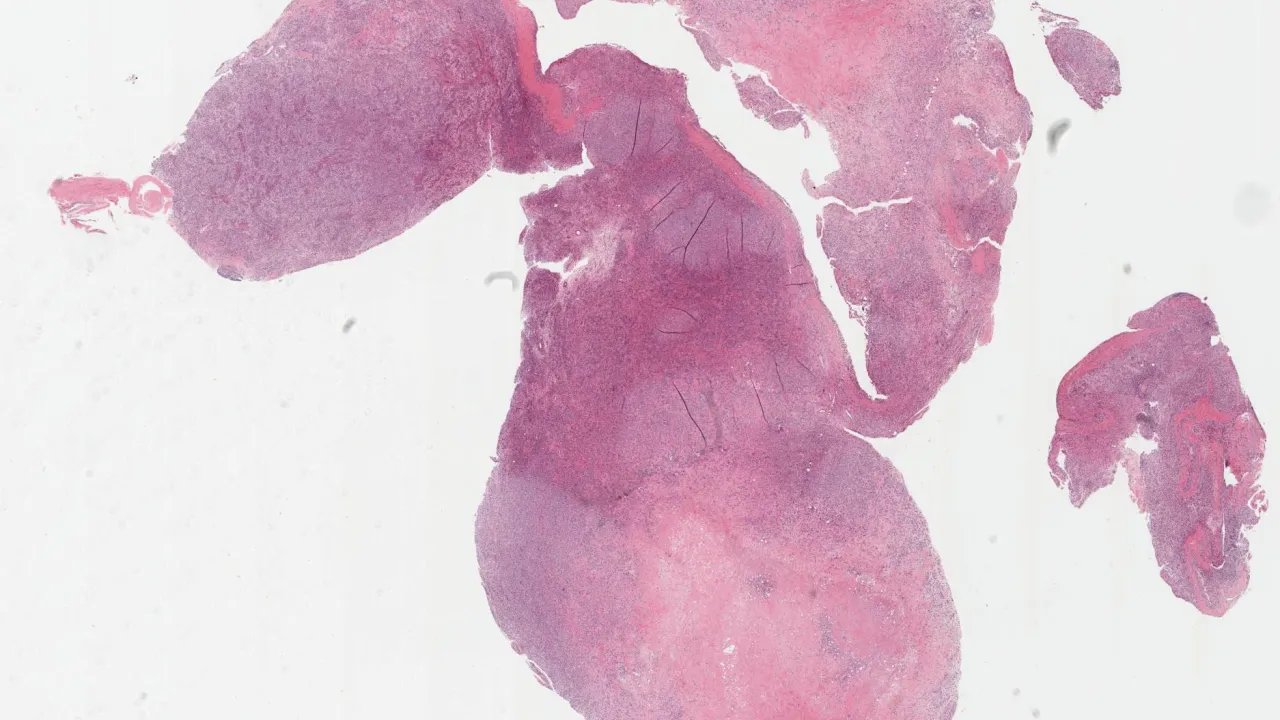

Oral Cavity, Burkitt lymphoma